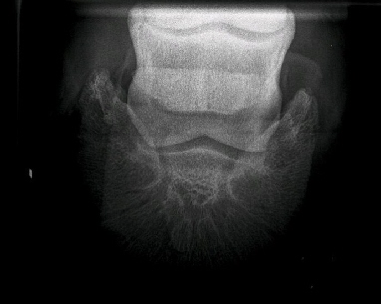

Digital radiography provides the highest quality image, allowing us to evaluate not only the bony structures of your horse's legs, head and neck but also some of the soft tissues! Digital imaging provides superior ability to manipulate the picture to see all the details. Whether examining teeth before a dental extraction, hunting down the cause of foot soreness, diagnosing sinus disease, guiding an injection of the neck, or evaluating a lacerated leg, digital imaging allows us to fully evaluate skeletal injuries and diseases.